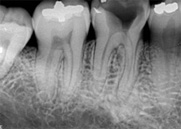

antes depois